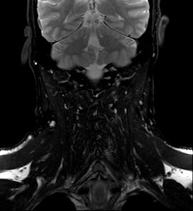

Prueba diagnóstica no invasiva que consiste en la obtención de imágenes de alta definición anatómica del cuello mediante el empleo de un campo electromagnético y ondas de radio (con un emisor y un receptor). No utiliza radiación ionizante. Indicaciones: sospecha de tumor, infecciones, ganglios. - Angio-RM intracraneal

Prueba diagnóstica no invasiva que consiste en la obtención de imágenes de alta definición anatómica del cráneo mediante el empleo de un campo electromagnético y ondas de radio (con un emisor y un receptor). No utiliza radiación ionizante. En ocasiones se deberá emplear contraste paramagnético (Gadolinio) para completar el estudio. - RM Cuello

Prueba diagnóstica no invasiva que consiste en la obtención de imágenes de alta definición anatómica del cuello mediante el empleo de un campo electromagnético y ondas de radio (con un emisor y un receptor). No utiliza radiación ionizante. En ocasiones se deberá emplear contraste paramagnético (Gadolinio) para completar el estudio.